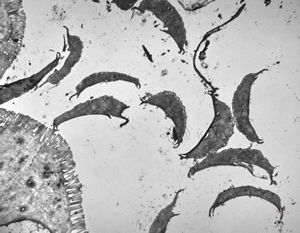

F,52y. | spirochetosis … colon (HE) … blue-stained brush border

F,52y. | spirochetosis … colon Warthin-Stary silver impregnation

F,52y. | spirochetosis - colon

F,52y. | colon … spirochetosis … subepitheliai microbes